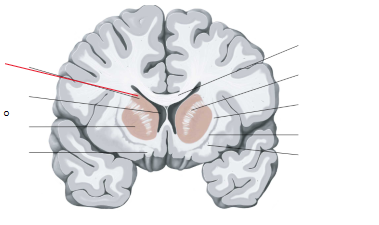

nucleus caudatus

putamen

globus pallidus

hippocampus

amygdala

laterale ventrikels (I en II)